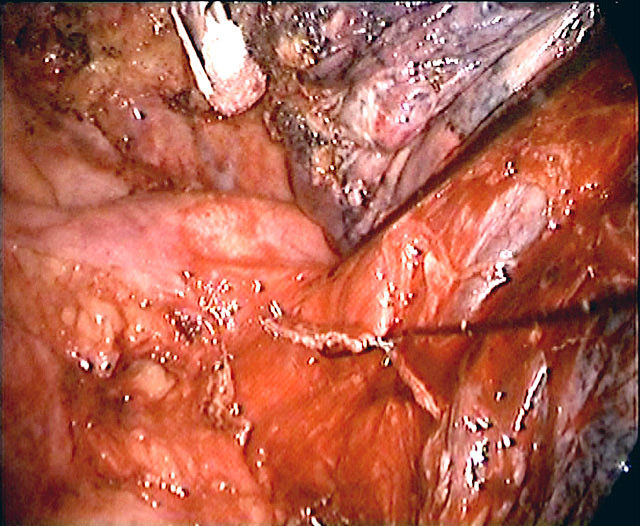

If there is no contraindication to proceed, a minithoracotomy (generally 6 to 8 cm in length) is placed over the fourth intercostal space in the anterolateral chest (Figure 2). In females, the skin incision can be made (if the anatomy allows) in the inframammary fold for cosmesis. The location of this wound usually means only a small portion, if any, of the latissimus dorsi muscle needs to be divided. The serratus anterior muscle is split along the direction of its fibers. Division of the intercostal muscles permits access into the pleural cavity. The placement of the minithoracotomy in this position provides direct access to the hilum, and because the anterior intercostal space is wider than the posterior space, it facilitates later retrieval of the specimen. We do not use rib spreader, only a soft tissue retractor for the minithoracotomy wound.

A sponge holding forceps is introduced through a separate tiny incision in the seventh or eighth intercostal space in the posterior axillary line. With two sponge holding forceps, one through the anterior minithoracotomy and the other through the posterior wound, the collapsed lung can be moved around and a thorough assessment made of the location and extent of the primary lesion. This technique also permits a search for associated pathology (satellite nodules; mediastinal or hilar lymphadenopathy which could be missed even by high resolution contrast chest CT).

Contrary to laparoscopic surgery, which generally does not allow digital palpation (because of the need to use valved ports to sustain carbon dioxide insufflation), digital palpation through the minithoracotomy, in addition to instrument palpation during VATS exploration, can provide valuable information to the surgeon and is encouraged. By bringing the lung towards the palpating finger placed through different sites, a large portion of the lung surface can be palpated. This is important as small nodules (< 0.5 cm) which are not subpleurally located would almost certainly go undetected by thoracoscopic examination alone.